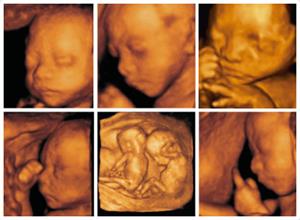

首先,做四维彩超是排除畸形的一种产检手段,高清的画质,全方位360°,是可以非常清晰的看到宝宝在妈妈肚子里的具体情况。做四维彩超的主要目的是排除畸形,保障母婴安全。

做大排畸一般是22-28周,因为在这段时间羊水比较充足,宝宝的骨骼发育的比较成熟,活动空间比较大,这样会看的清晰,更好的进行排畸,所以,在时间上一定要控制好,不要忘记了。

【温馨提醒】在做大排畸的过程,如果宝宝不配合的话,用手挡住了其他部位导致医生看不到,医生会叫孕妈妈到楼下走走,活动活动,然后在上去继续做,如果是这样,做的时间就会稍微长一点,一般的话15-20分钟可以做完的。